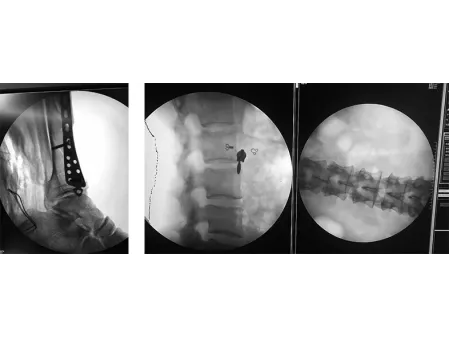

Gracias a su intensificador de imagen, este equipo de imagenología ofrece una visualización estable y de la mejor calidad, mientras reduce al mínimo la exposición a la radiación. Incorpora un generador de alto voltaje y tecnología de alta frecuencia que garantizan un rendimiento confiable incluso en los entornos quirúrgicos más exigentes. Su pantalla táctil LCD de 10.4 pulgadas es intuitiva, gira hasta 180° y está fabricada con materiales resistentes a la corrosión. Además, incluye un sistema de mensajes de error en chino lo que facilita la resolución de problemas para usuarios locales.

Inlcuye funciones avanzadas tales como fluoroscopía por pulsos y modo boost, para obtener imágenes claras y detalladas que permiten diagnósticos más seguros y procedimientos quirúrgicos más precisos. El diseño ergonómico incluye una manija para maniobras rápidas y una rueda con bloqueo de dirección que asegura estabilidad durante el uso. Su arco de 800 mm ofrece un amplio margen de movimiento para trabajar con mayor libertad. Además, cuenta con triple campo de imagen (9", 6", 4.5") para enfocar con precisión zonas específicas, una cámara CCD giratoria de 360° para una visión completa y rieles de guía lineal coreanos que facilitan un deslizamiento suave. Sus relés Omron contribuyen a reducir el ruido operativo y prolongan la vida útil del sistema.

El arco en C con intensificador de imagen es una herramienta clave en distintas áreas médicas y quirúrgicas. Gracias a su versatilidad, se emplea con frecuencia en quirófanos, salas de rayos X, áreas de urgencias y unidades especializadas en procedimientos vasculares e intervenciones mínimamente invasivas. Su utilidad abarca desde cirugías generales, ortopédicas y de columna, hasta intervenciones en urología, traumatología y cirugía torácica o abdominal. También es indispensable en procedimientos como la fijación de fracturas, estudios endoscópicos, angiografías discales y tratamientos vasculares como la angioplastia.